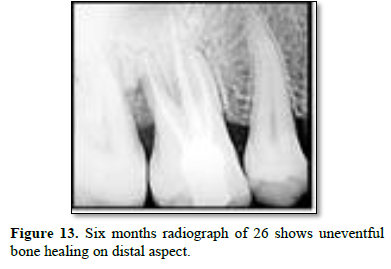

After 3 weeks of assessment, periodontal pocket was present on distal aspect of 26 and 36 (Figures 5 and 6). A full thickness mucoperiosteal flap was raised with respect to 25, 26, 27. The area was thoroughly debrided using hand curettes and ultrasonic scaler (Figure 7). Demineralized freeze-dried bone allograft was placed in relation to distal aspect of 26 (Figure 8). 10 ml of intravenous blood was collected in sterile tube and centrifuged to obtain the fibrin clot which was place on sterile dampen dish. Plasma Rich Fibrin Membrane (PRF) was placed to cover the graft (Figure 9) and simple interrupted suture were placed. Post-operative medications and instructions were given and patient was recalled after 7 days. Similar procedure was carried out for 36 after ten days (Figures 10-12). Patients were recalled after one week of surgical procedure for removal of sutures and evaluation of healing. Six-month recalls were scheduled for follow-ups. Radiograph was taken to assess the bone healing (Figures 13 and 14).

Distal aspect of 26 and 36 presented bone loss right up till the apex of the closest root. This would have led to necrosis of the teeth. Complete curettage after flap reflection resulted in smooth surface of cementum. DFDBA was used as a graft material due to its osteoinductive nature. Studies have shown promising results in repair of furacation and periodontal defects. It also has ability to stimulate cell attachment and cell migration and osteogenesis [5]. Plasma rich fibrin membrane was used as a barrier to prevent formation of long junctional epithelium. It has growth factors and act as a matrix for migration of endothelial cells and fibroblast thus promoting angiogenesis and also promotes formation of more resistant connective tissue [6]. Six months follow up radiograph shows optimum bone formation with distobuccal root of 26 and partial bone formation with distal root of 36 suggestive of healing lesion. There was also reduction in probing pocket depth and gingival healing. Similar findings were reported by George PM in 2017 with use of Osseo graft in endo-perio lesion. Six months follow up revealed improved clinical and radiographic findings [2].